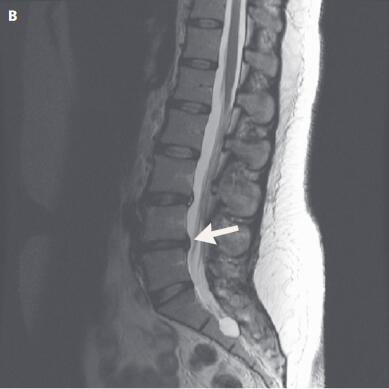

5个月后,第二次MRI(如下图B,重点在箭头所指)。

很明显,突出的腰椎间盘有所回纳。

也就是说,在不进行手术的前提下,只进行保守治疗,通过运动康复等手段,突出的腰椎间盘是有可能回纳(主要是指破裂的纤维环修复后生成新的水分液体的过程)